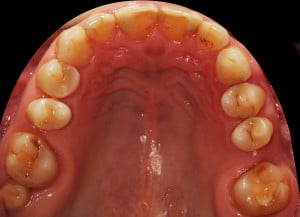

Do kliniki Stomatologia Bez Bólu zgłosiła się pacjentka, lat 61 z problemem nadwrażliwości zębów. Po przeprowadzonym wywiadzie stwierdzono spożywanie sporej ilości sezonowych owoców (truskawki, wiśnie, czereśnie, czarna porzeczka), nawet 3 razy dziennie. Następnie wykonano badanie wewnątrzustne. Stwierdzono obecność płytki nazębnej, ciemnego osadu oraz kamienia nazębnego na części trzonowców:

Wykonano higienizację jamy ustnej poprzez usunięcie kamienia nazębnego skalerem ultradżwiękowym, zdjęciem osadu i płytki nazębnej poprzez piaskowanie air flow plus oraz classic, a następnie wypolerowaniu gumką ze specjalistyczną pastą polerską: